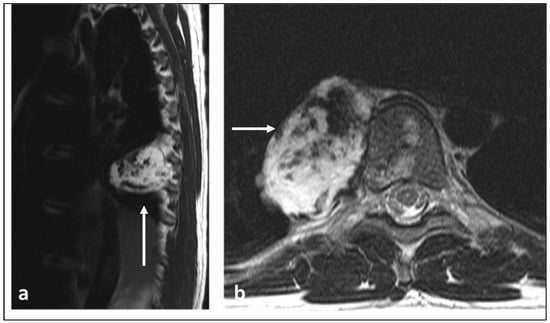

| Osteosarcoma | Osteoid matrix with sclerotic and lytic areas. Contrast can obscure osteoid matrix. | Extra-osseous soft tissue component. Low T2 signal foci corresponding to mineralisation. Secondary ABC change with fluid–fluid levels (this can be seen with telangiectatic osteosarcoma also). |